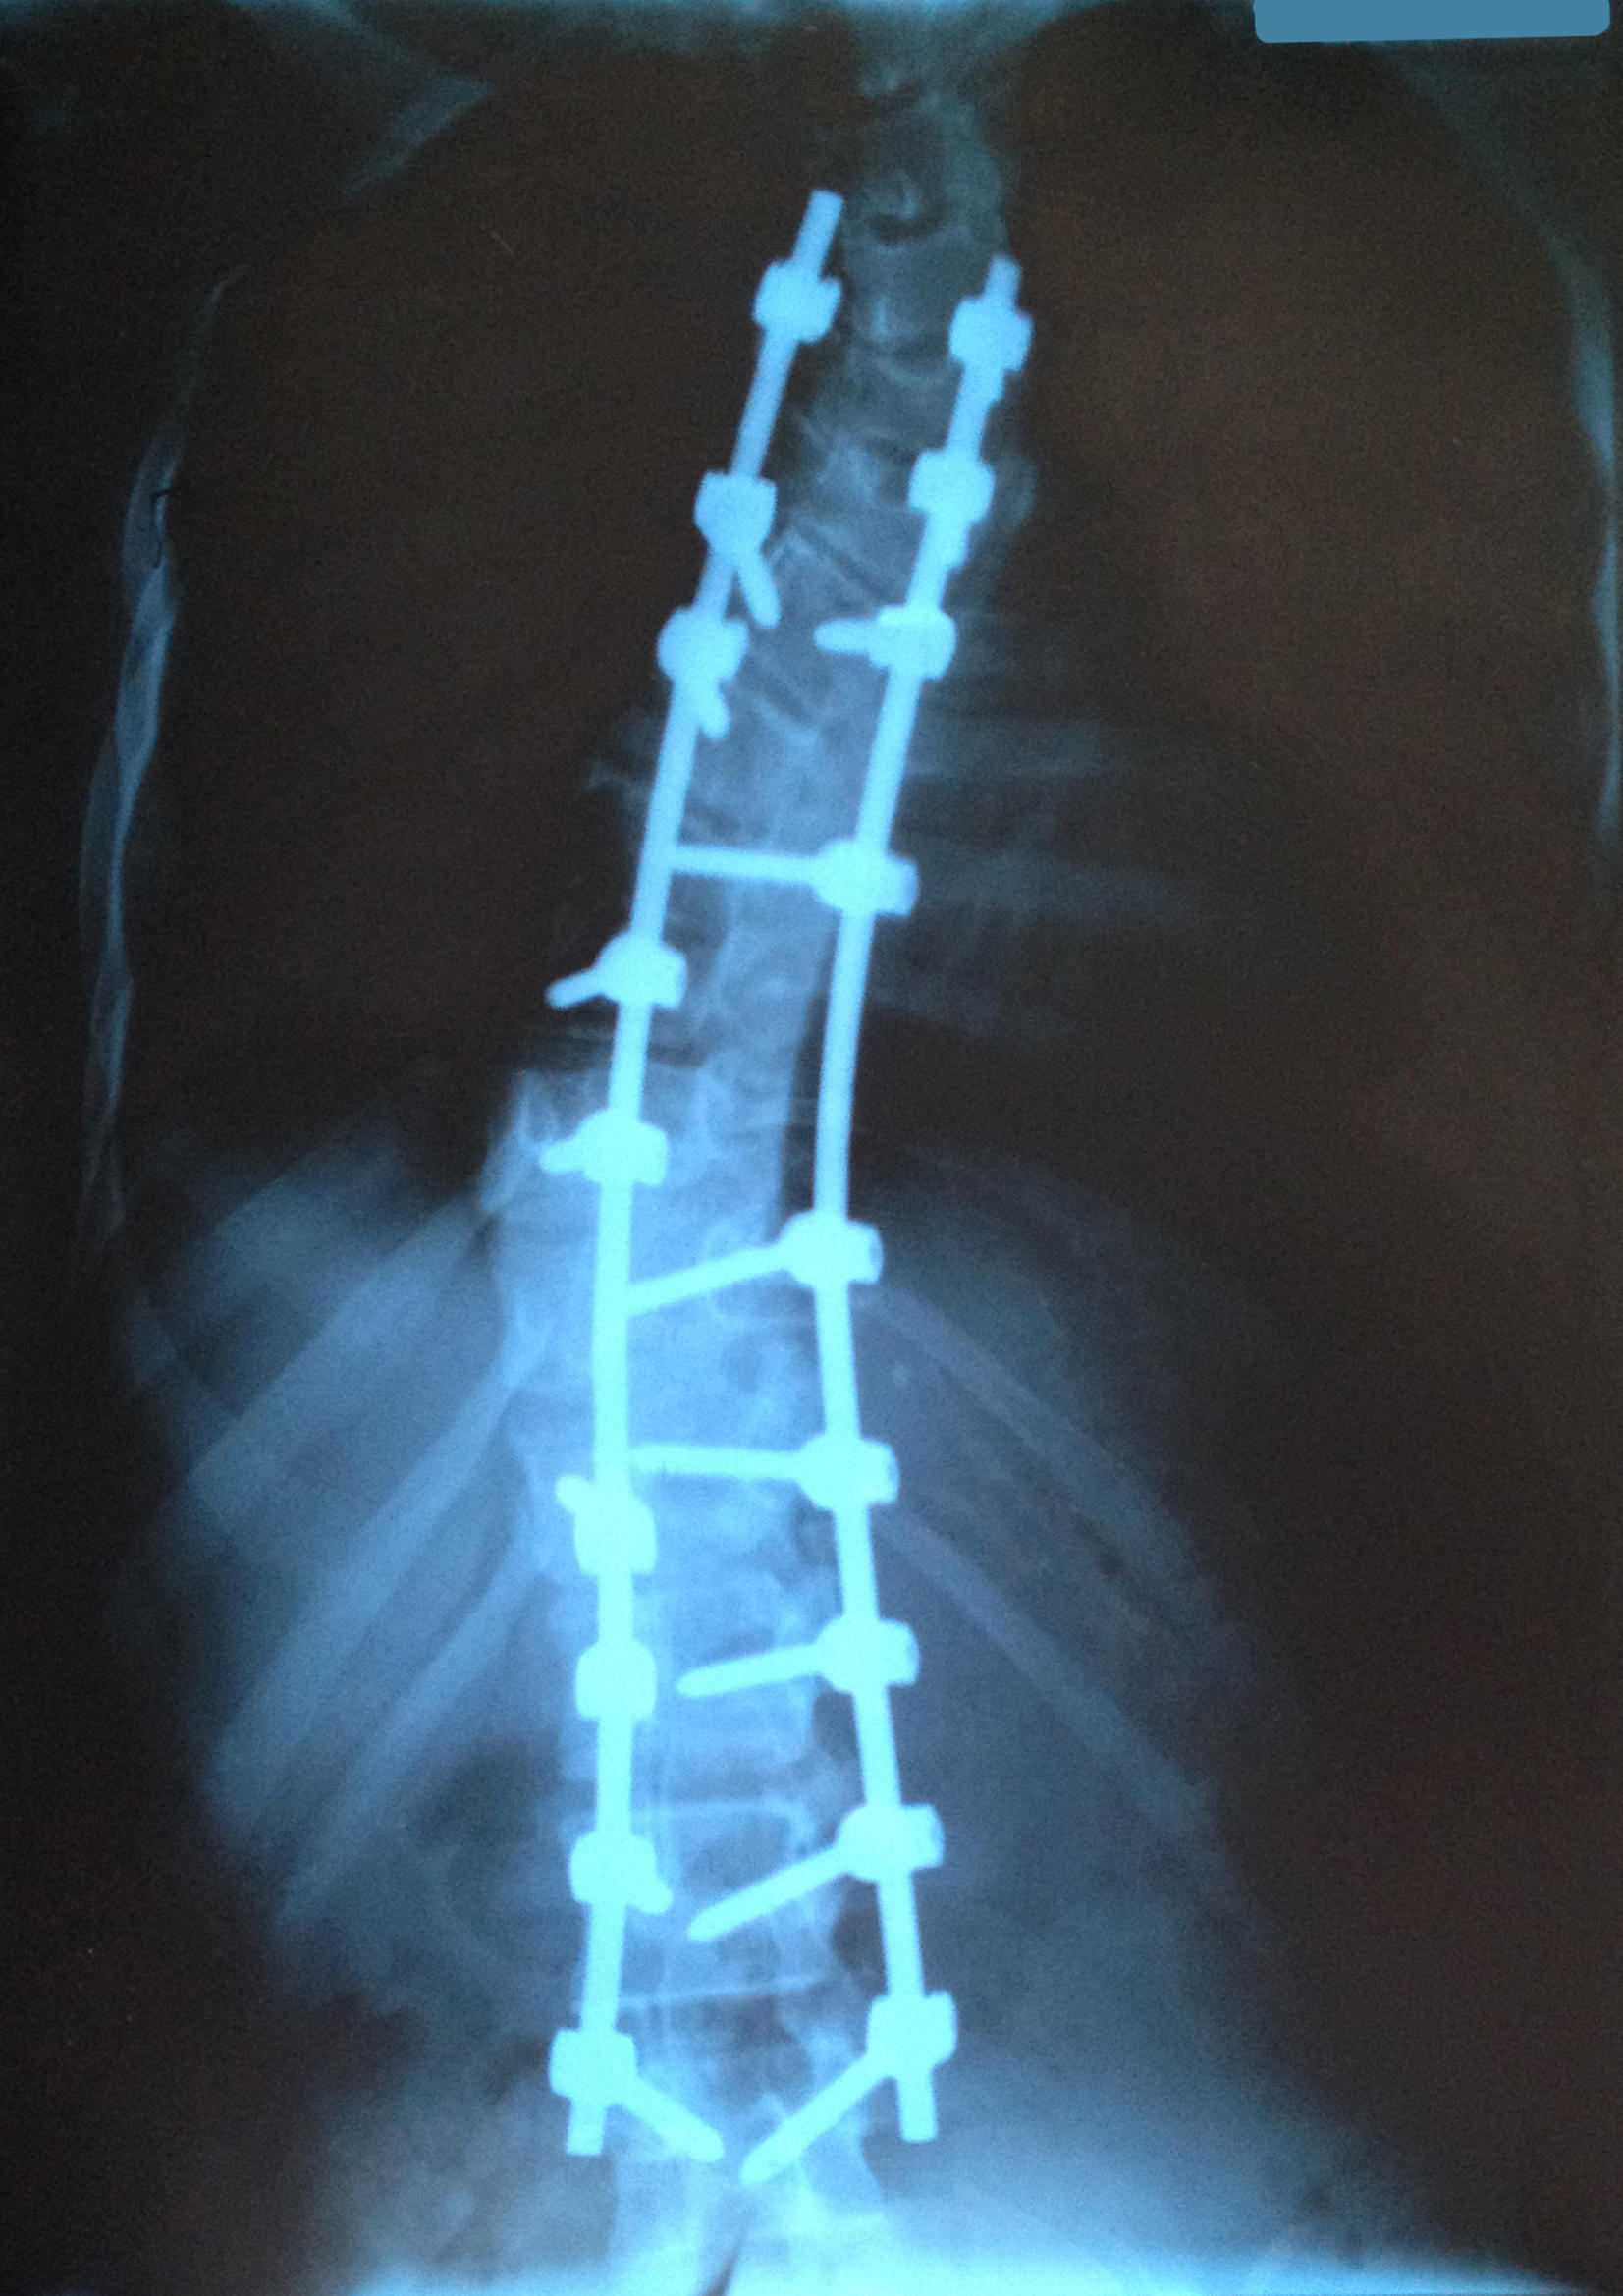

Перечитала тему, кое-что осталось за кадром. На операцию мы конечно не с третьей степенью отправились, к тому моменту резкая прогрессия привела нас в глубокую 4 степень, 84* в грудном отделе с начальной противодугой в шею... возникли серьезные проблемы со здоровьем, дыхательная недостаточность, проблемы с сердцем, питанием, генетики подтвердили дисплазию соединительной ткани, гипермобильность суставов, в частности синдром Марфана, синдром Элерса-Данлоса под вопросом. Сейчас большинство проблем снято. Остальное будем корректировать постепенно образом жизни, питанием и препаратами.

Refreshing, ди902, спасибо! Сейчас все уже хорошо. Поэтому, пройдя весь путь и набив кучу шишек в попытке любой ценой избежать операции, мой совет родителям сколиотиков, а особенно диспластиков - не бойтесь операции, не дотягивайте до серьезных градусов, операция сейчас и десять-двадцать лет назад - это небо и земля! А у подростков больше шансов исправить в дальнейшем реберные деформации без повторных операций чем у взрослых! Во вложении наши рентгены до и после. На год бы раньше прооперировать - могли бы выправить в ноль. Но и то, что сделано сейчас, это чудо! Для меня наши хирурги равные Богам)))

Zazell, тест Риссера 5, расти она перестала еще год назад, после операции стала выше на 6-7 см. Конструкция полностью титановая, и шурупы и стержни, всякое бывает... но без показаний снимать конструкцию не надо, только в случае поломок может быть перемонтаж или демонтаж если сформированы межпозвоночные блоки.